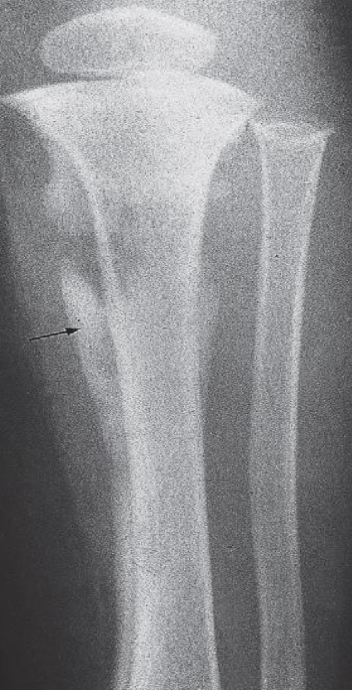

Osteomyelitis

- Destruction of the upper end of the tibia

- Periosteal reaction along the tibia.